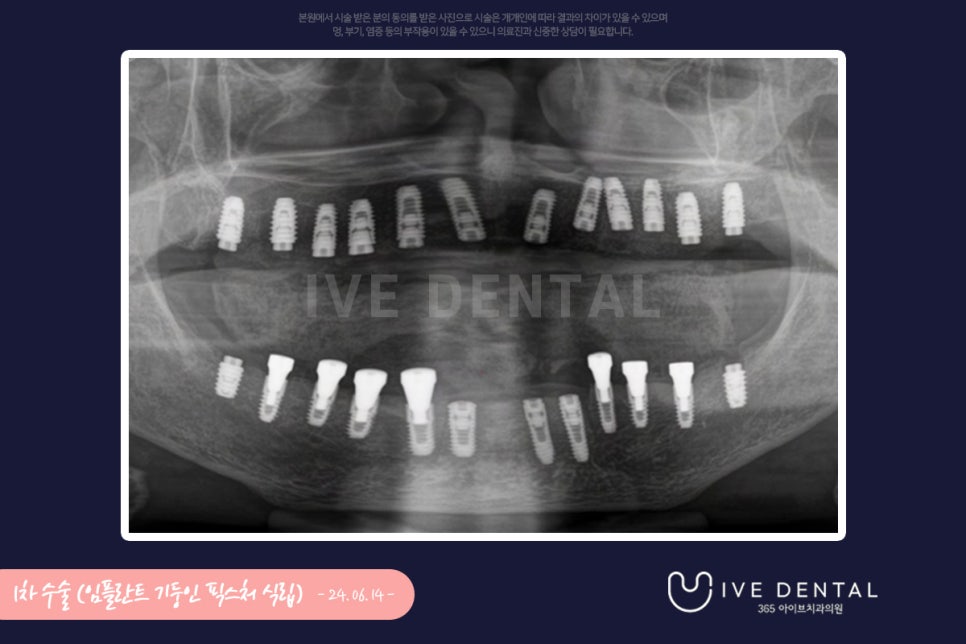

먼저 1차 수술로 임플란트의 기둥인 fixture 식립을 하였는데요.

임플란트의 기둥이 되는 이 fixture 식립이 무엇보다 중요하다고 할 수 있습니다.

환자분의 잇몸 상태가 좋지 않으셔서 뼈이식, 상악동 거상술 등 추가 수술도 같이 시행되었고

그냥 무작위로 심는 것이 아닌 환자분의 전체 구강 상태를 디자인하여 위와 같은 표대로 하나하나

다른 사이즈의 임플란트 fixture를 식립하게 됩니다.

이렇게 세밀하게 치아의 배열에 대해 디자인하여 수술해야만 다음에 전체적인 결과가 좋게 나오게 됩니다.